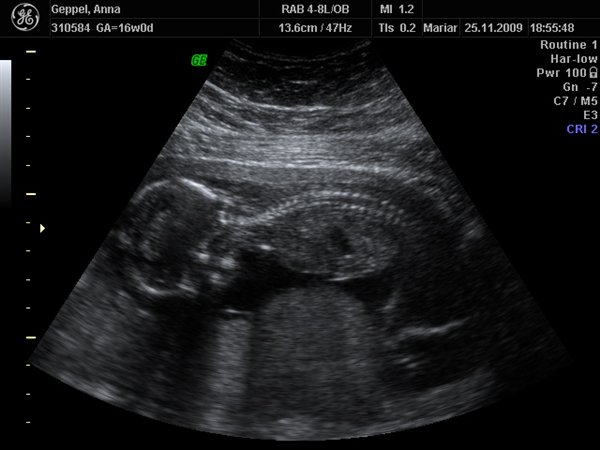

På billede nr. to ligger han på maven og man kan tydeligt se rygraden hele vejen fra nakken og ned.